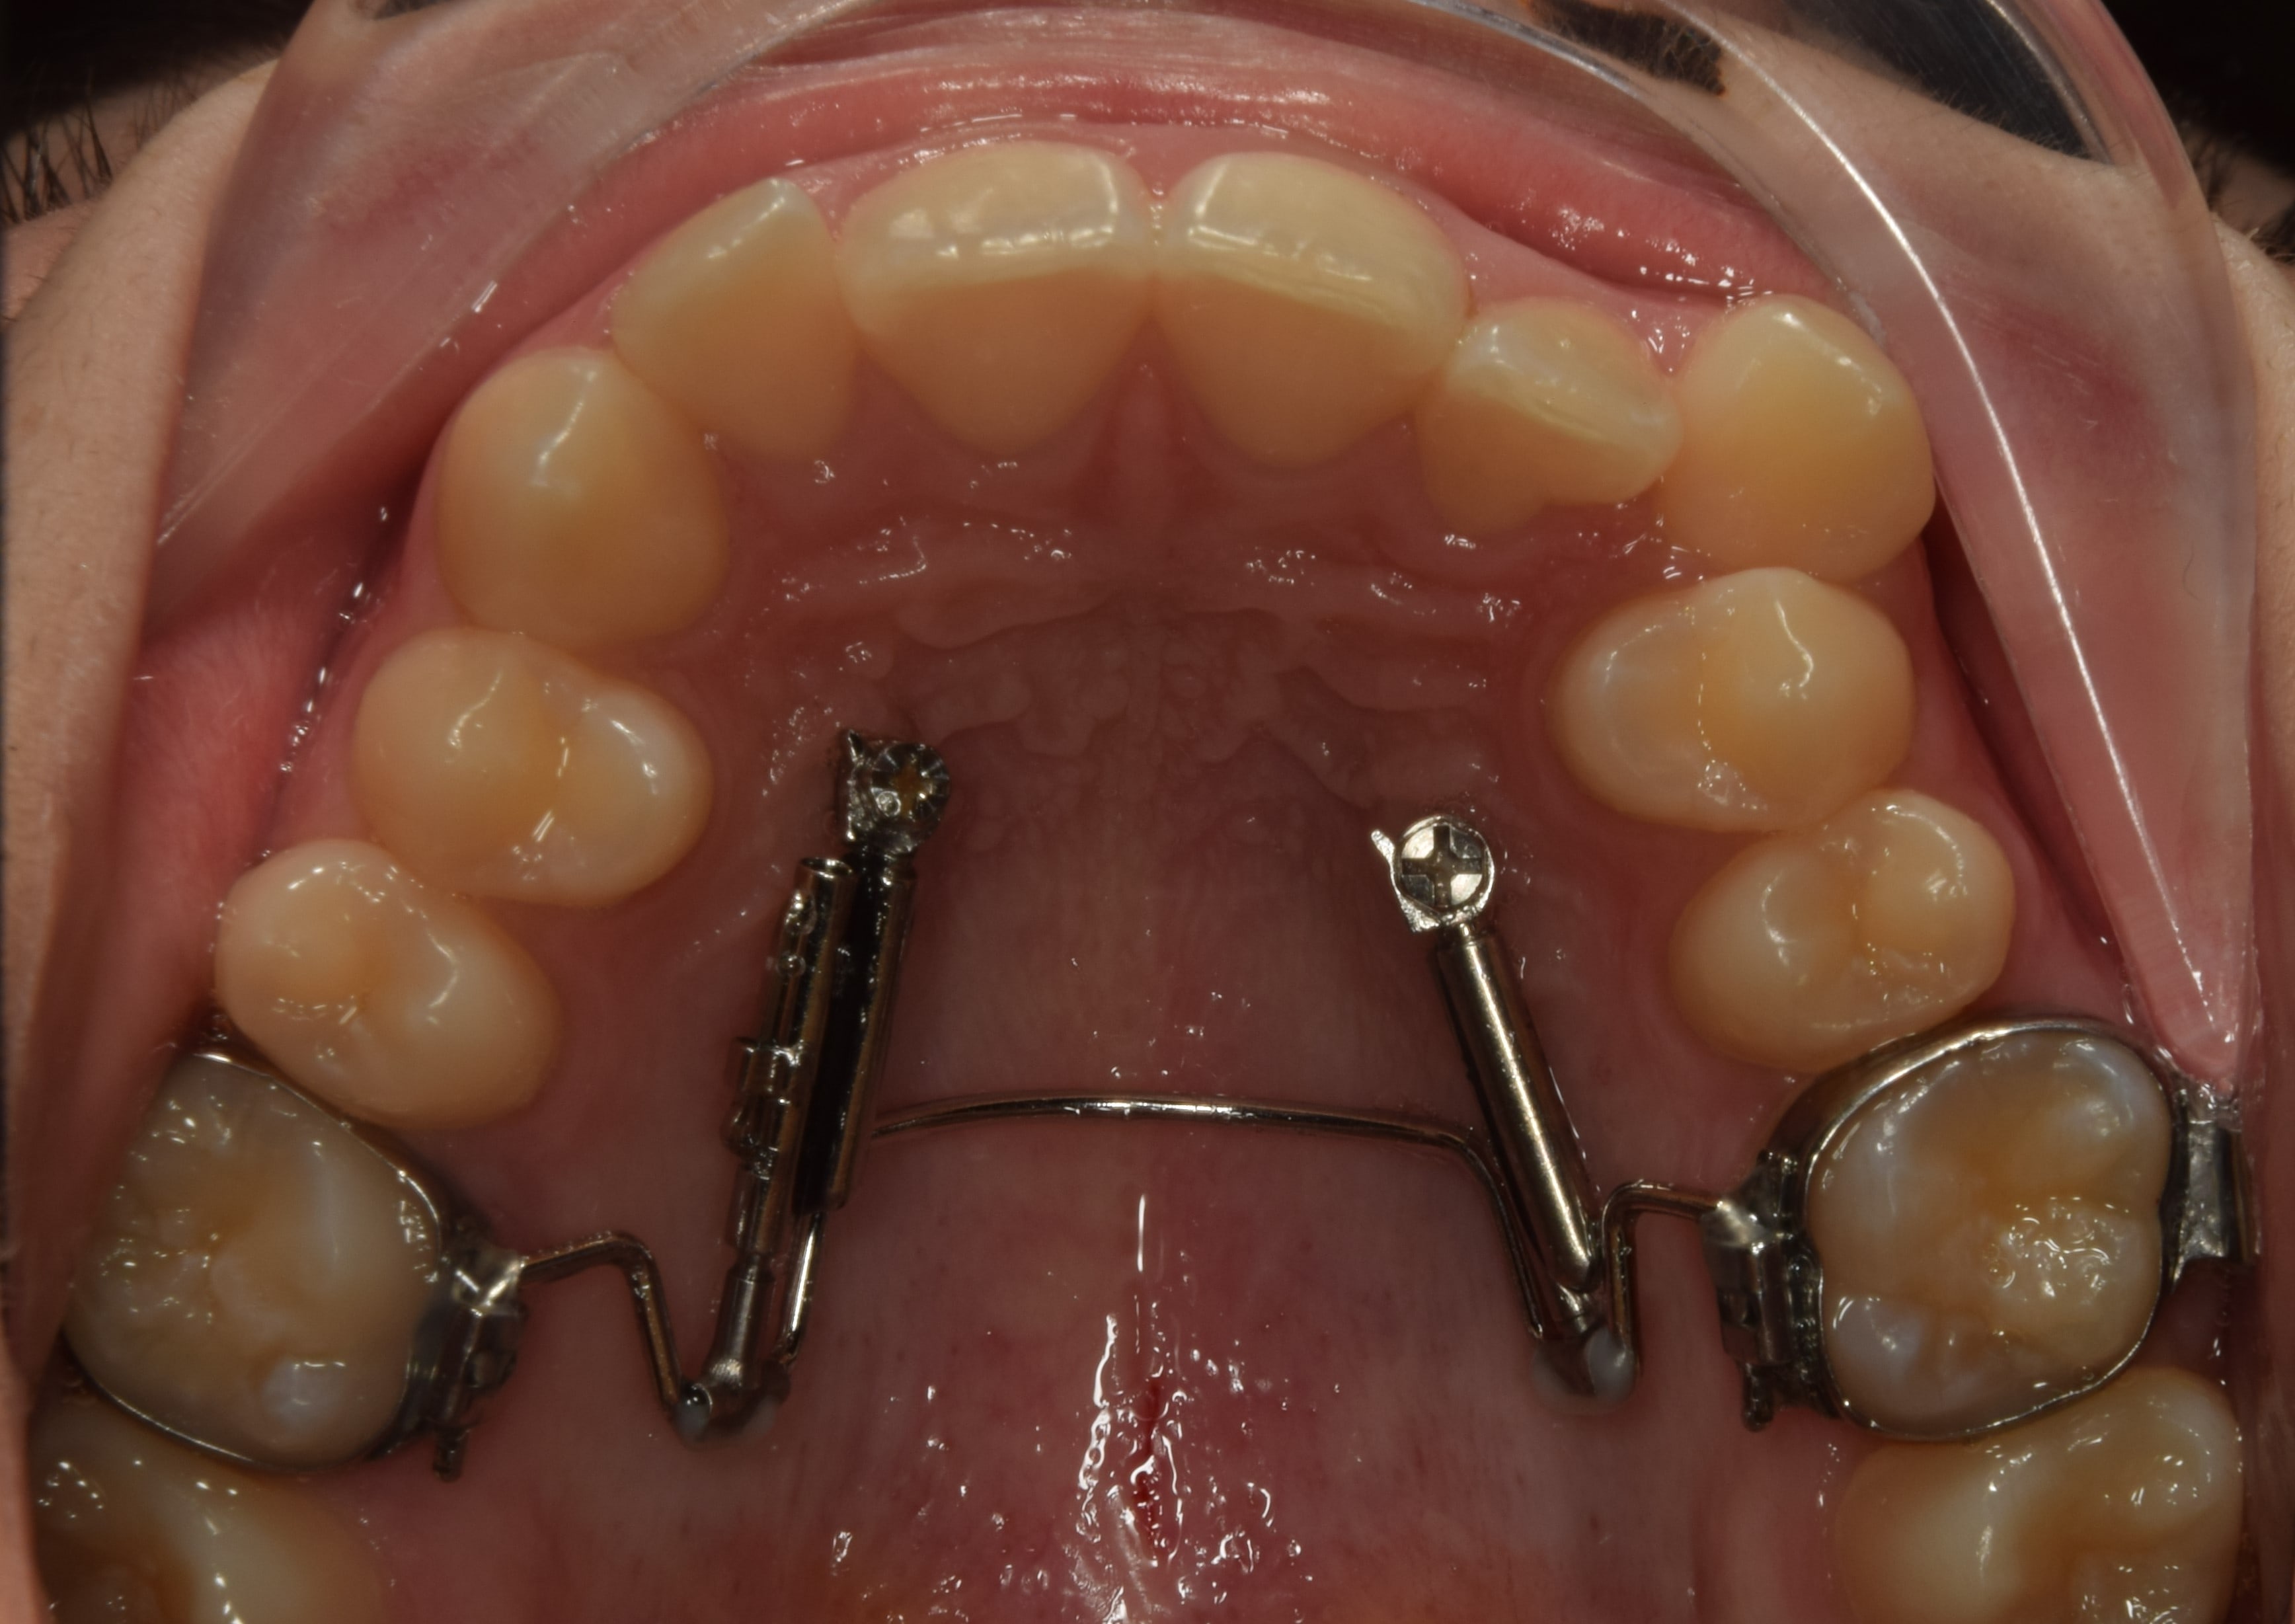

2. Jóval gyakoribb a szájpad különböző területeire behelyezett miniimplantátumok segítségével történő disztalizálás. Végtelen számú készülék van erre a célra, én a TOP JET disztalizálót használom. Ez két darab, a felső szemfog-első kisőrlő szájpadi oldalára betekert miniimplantátumból, két darab rugós teleszkópból, valamint egy a felső első őrlőfogakon gyűrűvel rögzülő, szájpadot áthidaló acélívből áll. Előnye, hogy a szájpad ezen részén nagyon megbízható, kiváló minőségű csontállomány található, a kezelés kiszámítható, illetve egyedülálló tulajdonsága, hogy nincs szükség fogtechnika bevonására (legfeljebb a szájpadív+gyűrű elkészítésére, de a készülék maga előregyártott, egyszerűen adaptálható). Hátránya, hogy igen drága. Sikerességi rátája 95% fölötti.